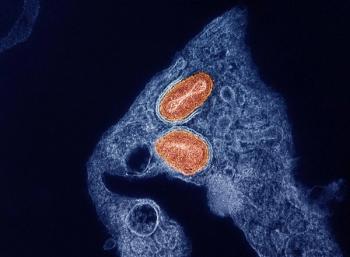

The Louisiana Department of Health announced the news late yesterday, and it is the first death in the US associated with the H5N1 virus.

Governor Newsom declares support for state response as bird flu spreads across the US among dairy cows and humans, with California leading the nation in cases.

If confirmed by the CDC, these cases would increase the national total of human infections to 60, with 58 already reported in various states.